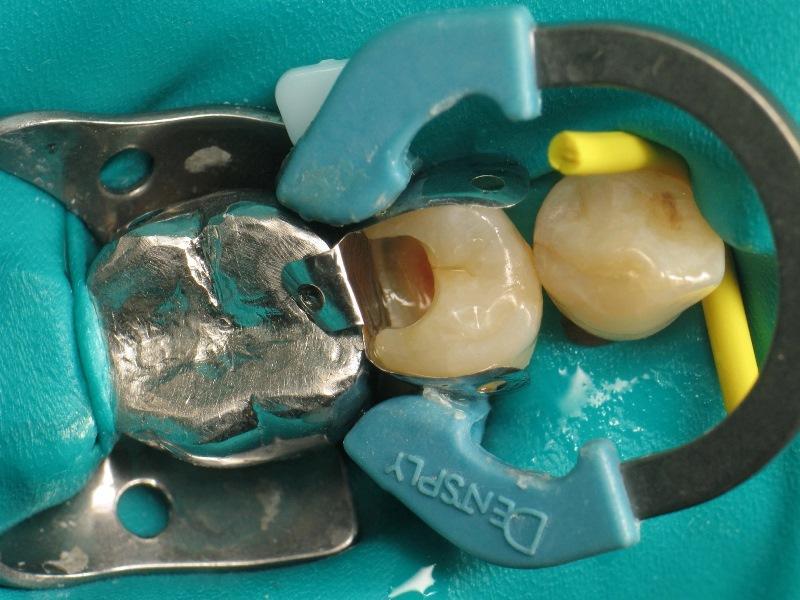

Фото 2: Наложение коффердама.

Фото 4: Установка проксимальной матрицы.